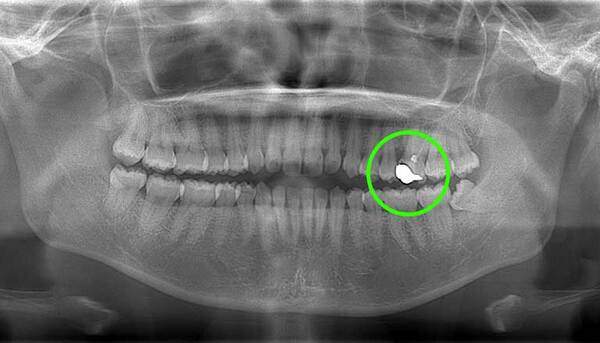

上顎はしっかり親知らずがはえています。下顎は右側は(青色)しっかりはえていますが、虫歯になっています。下顎の左側(赤色)は斜めにはえています。またこちらも虫歯になっています。

この場合、右側上下は残して、左側上下は抜くことがファーストチョイスになります。しかし、左上の6番目の歯(緑色)は根の治療をしており、虫歯にもなっていそうですので、左上の親知らずは移植歯として残しておいても良いという判断になります。

もちろん、患者様が移植は考えてなく、抜歯をしたいということであれば、抜歯を行います。